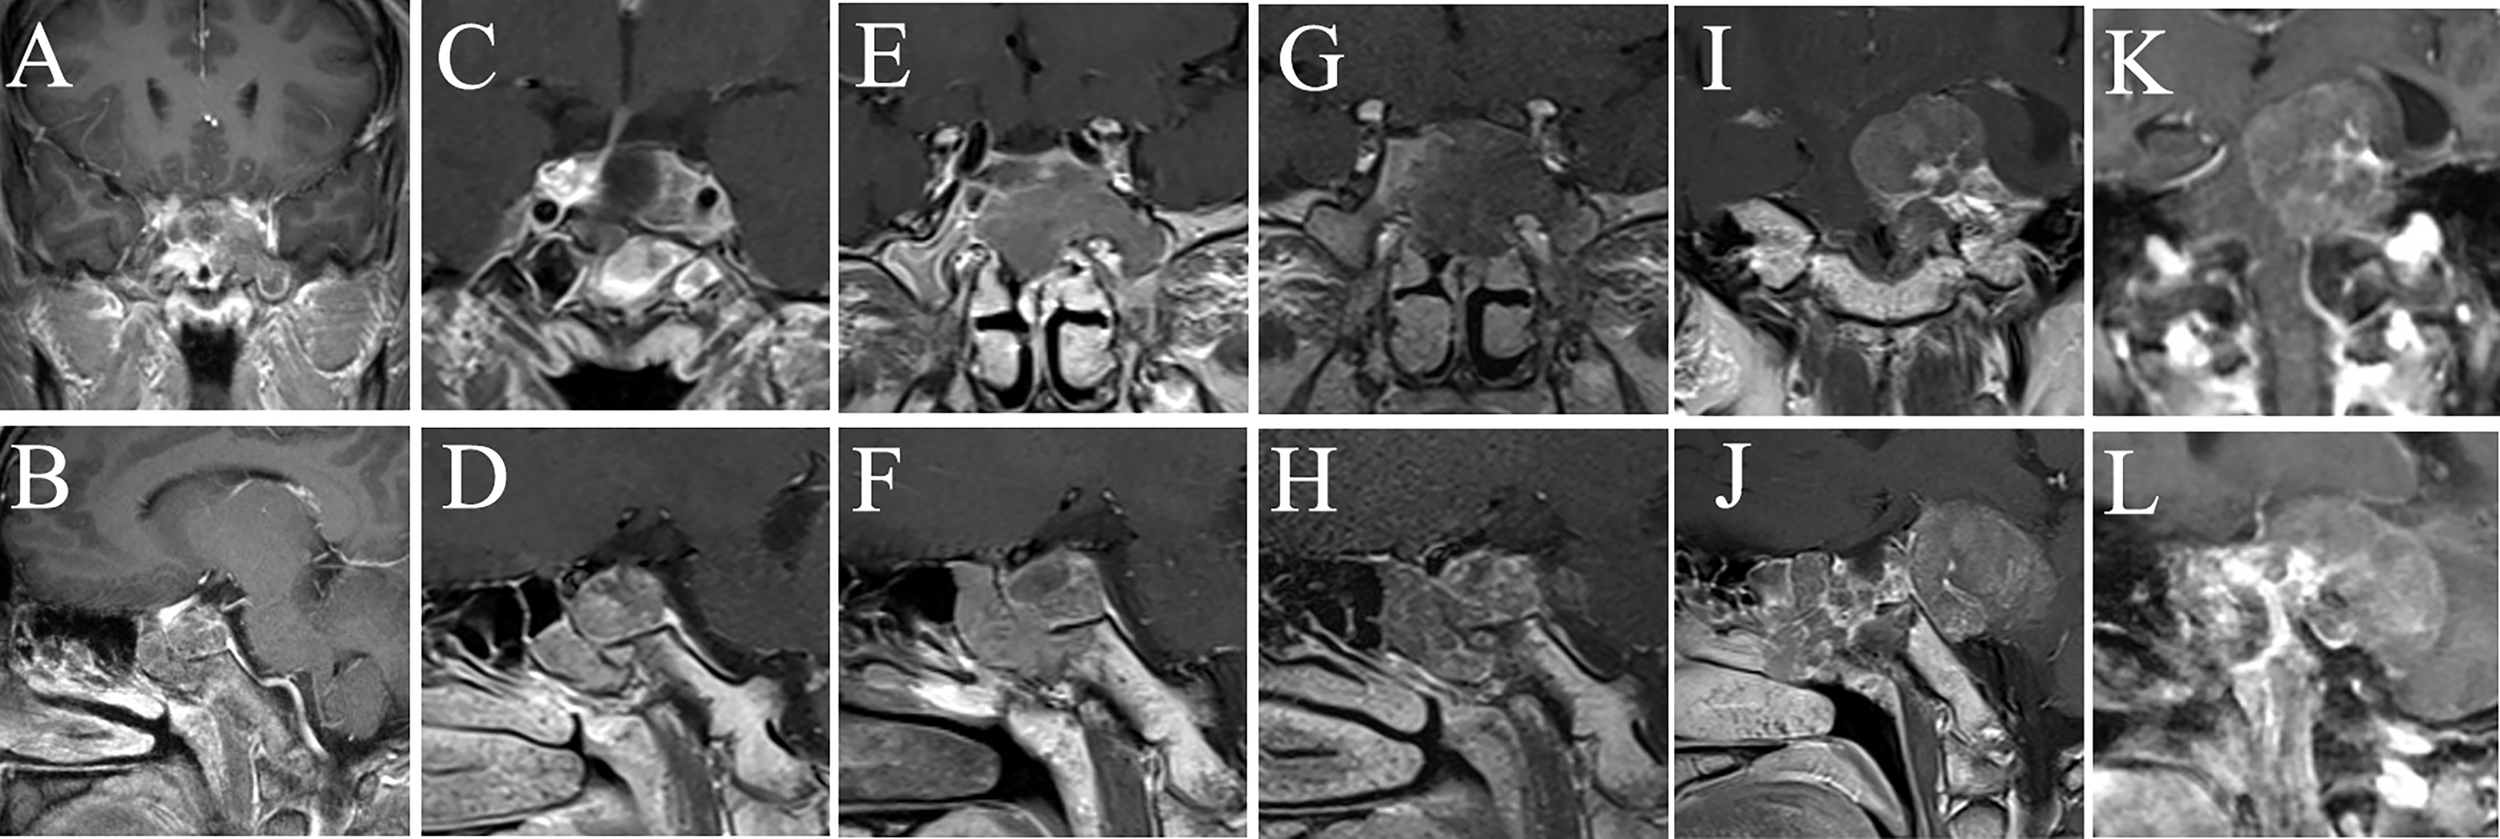

Figure 2

MRI examination of case 1. The images show the patient’s coronal and sagittal MRI of the head before (A, B), one week after (C, D), six months after (E, F), eight months after (G, H), sixteen months after (I, J), and seventeen months after (K, L) the fourth surgery, respectively.